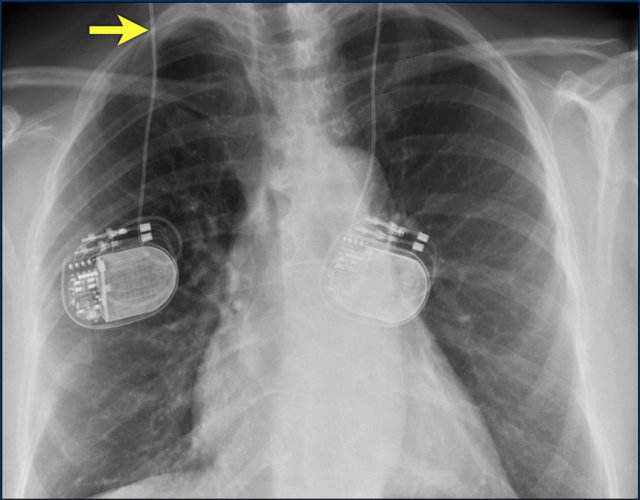

The images show a pacemaker with an atrial and ventricular lead.

The tip of the atrial lead is pointed upward and anteriorly, because the ideal position is in the right atrial appendage, where it is anchored within the coarse trabeculae.

The tip of the ventricular lead is positioned in the apex of the right ventricle, which is located to the left of the spine on a frontal chest X-ray and anteriorly on a lateral view.

Here an example of an ICD with wires in the right atrial appendage, the apex of the right ventricle and a lead to the left ventricle in the posterior coronary vein.

You can recognize the two shock coils of the ICD as thicker white bands along the course of the lead.